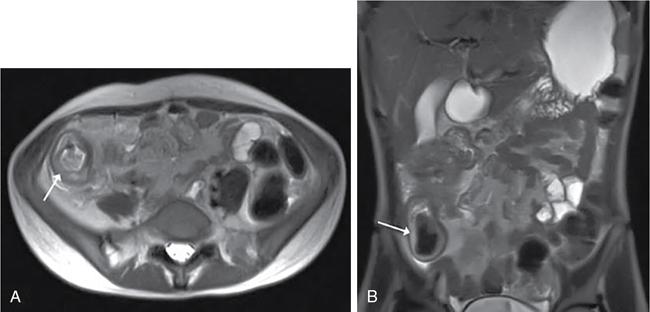

Kavita Saggar, Archana Ahluwalia, Devinder Pal Singh Dhanota, Geetika Khanna, Chander Gupta Inflammatory bowel disease (IBD) represents chronic idiopathic inflammation of the gastrointestinal [GI] tract. The common subtypes are Crohn’s disease, ulcerative colitis (UC) and indeterminate colitis (Fig. 7.11.1). Approximately 20%–25% of patients present in childhood or adolescence. Of these, nearly two-thirds of cases are caused by Crohn’s disease with an incidence of 4.56 per 1000,000 children (Fig. 7.11.2). IBD can affect any portion of the GI tract; however, children have a much higher incidence of small bowel and colonic involvement (Table 7.11.1). Currently, there is no single diagnostic test for the evaluation of IBD. Diagnosis is based on a combination of history, physical examination, serum inflammatory markers, endoscopy, histopathology and imaging. A host of imaging modalities is available for the evaluation of IBD in children. Traditionally, barium fluoroscopic studies, namely small bowel follow-through or small bowel enteroclysis (SBE) were used. However, barium studies depict only the mucosal abnormalities and do not evaluate the extraluminal extent of disease. Ultrasonography (US) is increasingly being used in the workup of patients with IBD. Small intestine contrast ultrasound (SICUS) and contrast-enhanced ultrasound (CEUS) are used for evaluation of IBD. CEUS requires intravenous administration of microbubble contrast such as Sonovue, and SICUS requires small bowel adequate luminal distension with ingestion of an iso-osmolar contrast agent such as polyethylene glycol. A recent meta-analysis of 33 studies showed that CEUS had better accuracy than US, CT and MR for the detection of inflammation and differentiation of fibrotic and inflammatory strictures. However, the extent of the disease was better evaluated by CT and MR. Currently, computed tomography enterography (CTE) and magnetic resonance enterography (MRE) have emerged as the most effective tools for imaging small bowel in patients with IBD. CTE and MRE can accurately depict the spectrum of imaging findings related to severity, extent and complications of IBD and thereby help in guiding management and assess the response to treatment. MRE is an attractive imaging modality due to lack of ionizing radiation, inherent multiplanar capability and excellent soft tissue contrast resolution. In addition, dynamic/cine imaging allows assessment of peristalsis and accurate identification of the diseased segment. The major disadvantage of MRE is high cost, lower spatial and temporal resolution and long examination time. Crohn’s disease is a transmural granulomatous disease that can affect any part of the GI tract from the oral cavity to anus, often involving multiple discontinuous segments of bowel. Patients have a genetic predilection to develop an abnormal immunologic response to environmental factors including food and gut flora, leading to a chronic inflammatory response. Small bowel is the major site of involvement. Terminal ileum is the most common location which is involved in approximately one-third patients. The colon is affected in 50% patients. In 15%–20% cases, there may be isolated involvement of the colon without affecting the small bowel. The clinical importance of small bowel Crohn’s disease is the impact that a diffuse small bowel disease is expected to have on child’s growth and development. Thus, objective evaluation of small bowel is essential in differentiating from other enteropathies and in directing the management of patients with IBD. Two methods used for imaging small bowel with barium using fluoroscopy are standard small bowel follow through (SBFT) and SBE. Small bowel evaluation with barium has long been considered the most common, noninvasive, inexpensive and easily accessible radiological method, but it has been replaced by cross-sectional imaging. In the current scenario, the only indication of barium studies is when CTE or MRE cannot be done because of nonavailability or are not feasible. Ultrasound is being increasingly used to assess the activity of Crohn’s disease, especially in paediatric patients. Greyscale ultrasound allows morphologic assessment of bowel wall and mesentery. Normal small bowel loops are easily compressible with the transducer and the wall thickness is <2 mm. The bowel loops show regular peristalsis and are mobile. Colour Doppler shows minimal intramural or perienteric vascularity. The salient sonographic features of Crohn’s disease are: There is marked concentric or eccentric bowel wall thickening [>2.5–3 mm]. The mural echogenicity depends upon the degree of inflammation and fibrosis. In the acute phase, mural stratification is maintained (Fig. 7.11.3A and B). In patients with long-standing disease, a target or pseudo-kidney appearance may be seen. In long-standing burnt-out disease, there is submucosal fat deposition. The actively inflamed bowel segments show increased vascularity on Doppler ultrasound (Fig. 7.11.4A and B). CEUS with microbubbles can objectively assess the disease activity. A stricture is seen as a segment of bowel wall thickening with apposition of the luminal surfaces. There is persistent luminal narrowing with variable degree of upstream dilatation and hyperperistalsis. Doppler imaging reveals hyperemia in strictures with an active inflammatory component. Fibrotic strictures do not demonstrate increased blood flow. A major advantage of ultrasound is real-time imaging which allows the evaluation of bowel peristalsis. The diseased segments of the bowel (inflamed or fibrotic) show reduced peristalsis and often appear fixed in position. Mesenteric inflammation is commonly seen in active Crohn’s disease. Sonography reveals thickening of mesentery with heterogeneous echogenicity due to oedema. Doppler ultrasound shows increased vascularity due to engorgement of vasa recta. Fibrofatty proliferation of mesentery seen in chronic disease appears as abnormally thickened echogenic fat that displaces the bowel loops. Reactive mesenteric lymph nodes (up to 1.5 cm) can be seen in the active inflammatory phase of Crohn’s disease. These appear as hypoechoic round or oval structures with preserved fatty hilum. Sinus tracts and fistula often arise from or just proximal to a strictured segment and appear as linear areas of altered hypoechogenicity extending from serosal surface of gut. There may be tethering and/or angulation of the affected bowel segment. Abscesses are discrete well-defined fluid collections with internal debris, septation or nondependent echogenic gas. Colour Doppler reveals peripheral hyperemia with absent blood flow centrally. Ultrasound may be falsely negative if an abscess contains a large amount of air and can be mistaken for an air-filled bowel loop. Both CTE and MRE identify the transmural, extramural and mesenteric manifestations of small bowel Crohn’s disease. The imaging findings can be categorized as: Asymmetric long segment (>3 cm) bowel wall thickening is a consistent feature of Crohn’s disease. The mesenteric border is usually more severely affected. It is imperative that the bowel should be distended when assessing bowel wall thickening. Thickening may be mild (3–4 mm), moderate (5–10 mm) or severe (>10 mm) (Fig. 7.11.5A and B). This is the most consistent finding in the active inflammatory stage, defined as increased signal intensity or attenuation on contrast-enhanced scans in a noncontracted segment of bowel in comparison with adjacent small bowel segments. Hyperenhancement may be stratified into bilaminar and trilaminar patterns. In the bilaminar pattern, there is hyperenhancement of only the inner wall (often referred to as mucosal hyperenhancement), and in the trilaminar pattern, there is inner and outer wall hyperenhancement, with the submucosal oedema giving a halo effect. Hyperenhancement may also be homogeneously transmural or patchy. A potential pitfall in contrast enhancement is that normal jejunal loops enhance more than ileal loops and collapsed bowel segments can show apparent hyperenhancement (Figs. 7.11.6A,B and 7.11.7A–C). These are defined as multifocal (>3) segmental areas of involvement with normal intervening gut loops. This is an important feature that differentiates Crohn’s disease from UC when colon is predominantly involved (Figs. 7.11.5A,B and 7.11.7A–C). This is identified as an increased signal of the thickened bowel wall on T2W images. The inflamed walls also show restricted diffusion. The hyperintense signal due to intramural oedema persists on T2W fat-saturated images differentiating it from intramural fat seen in long-standing burnt-out disease (Fig. 7.11.8A and B; refer Fig. 7.11.20A–D).